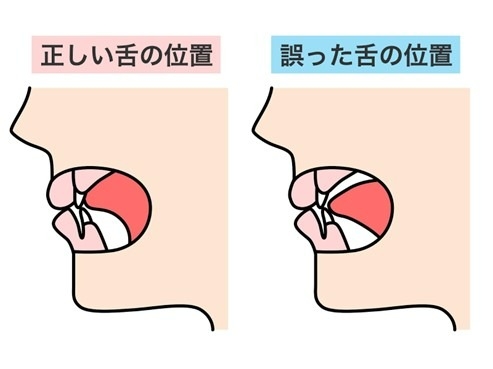

Q.舌にできる、ギザギザした跡は何? - 新浦安の歯医者・歯科栗林歯科医院各専門医在籍。

知っておきたい「正しい舌の位置」セルフチェック法と舌癖改善トレーニング方法を解説 - 東京日本橋エムアンドアソシエイツ矯正歯科。

Q.舌にできる、ギザギザした跡は何? - 新浦安の歯医者・歯科栗林歯科医院各専門医在籍。

ベロの横が波うっている!舌圧痕の2つ原因 – さいたま市岩槻区審美歯科のスワンデンタルクリニック。